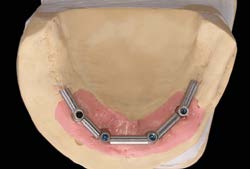

Các Implant ngắn 6.5mm BTI được đặt bằng cách sử dụng quy trình khoan định hướng sinh học (biologically guided drilling protocol) độc quyền của BTI, với lực vặn chèn được đo tại thời điểm đặt để xác nhận sự phù hợp cho việc chịu lực tức thì. Các phục hình tạm thời liên kết bắt vít được gắn ngay sau phẫu thuật để ổn định sự phân bố lực trong quá trình tích hợp xương. Từ 3 đến 6 tháng sau, chúng sẽ được thay thế bằng các cầu răng sứ kim loại cố định hoặc phục hình lai kim loại-nhựa, đảm bảo phục hình hoàn hảo cho bệnh nhân tiêu xương dọc.

Có 18 bệnh nhân đã nhận 36 Implant ngắn 6.5mm BTI phục hình liên kết dưới dạng chịu lực tức thì. Thời gian theo dõi trung bình là 8.02 ± 1.47 năm (dao động từ 6 đến 10 năm).

- Tất cả các trụ Implant đều đạt độ ổn định ban đầu đủ cho quy trình chịu lực tức thì, với lực vặn chèn trung bình là 42.8 ± 12.6 Ncm.